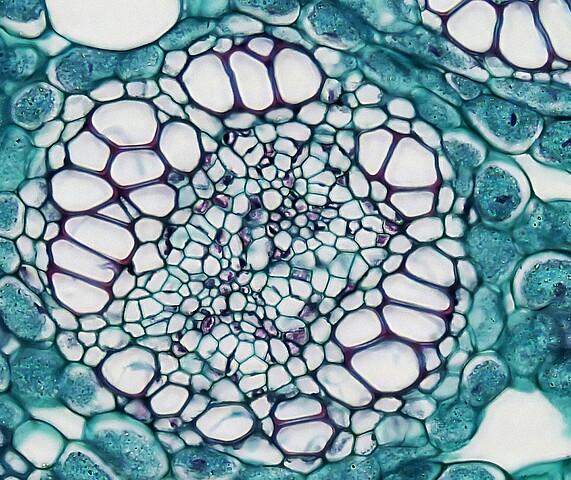

Cellectric Biosciences

Das Wiener Deeptech-Startup Cellectric Biosciences revolutioniert die Biowissenschaften – mit einer Technologie, die elektrische Felder nutzt, um Zellen gezielt zu analysieren und zu beeinflussen.